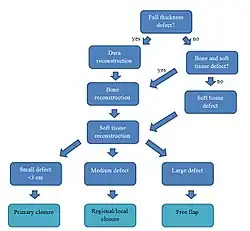

On the flowchart, a simplified algorithm for scalp reconstruction is depicted. The options range from simple solutions for small skin defects to complicated reconstructions requiring multi-tissue reconstructions.